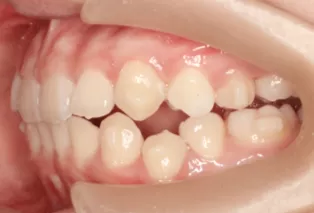

Intraoral photos